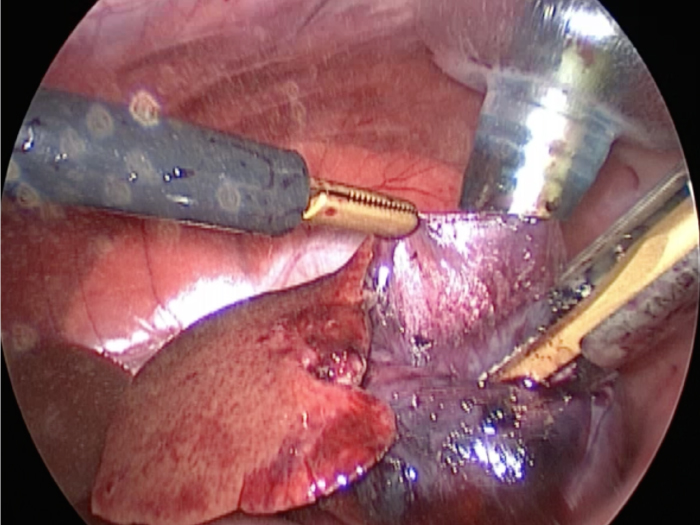

胆嚢の頸部に糸を通し動脈を確保しています。

総胆洗浄をして詰まりがないかまずは確認します。(右)

きれいに開通していました。鉗子が大きく感じますが体が小さいので大きく見えます。